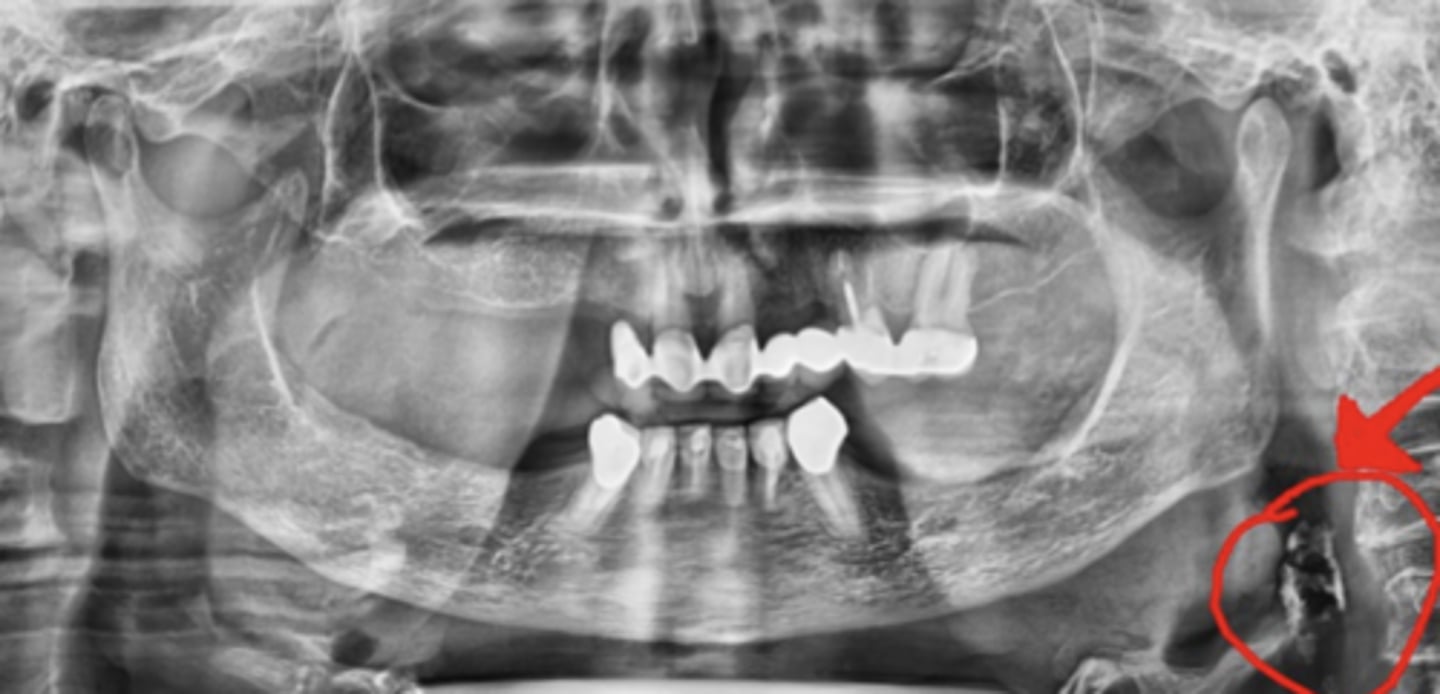

Multiple small radiopacities superimposed over mandibular ramus, can be uni or bilateral

What are carotid artery calcifications?

Where do carotid artery calcifications appear radiographically?

What is stylohyoid ligament calcification?

How does stylohyoid ligament calcification appear radiographically?

Linear radiopacity extending from skull base toward hyoid